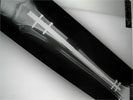

Post

Op

Intramedullary bone lengthening using Fitbone nail to correct 5cm tibia shortening

Progress

Distraction of osteotomy site and tibia lengthening